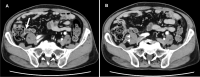

Case presentation: A 72-year-old male was referred to our hospital to examine the cause of hematochezia. A colonoscopy study showed a protruding lesion resembling a submucosal tumor (SMT), approximately 20 mm in diameter, at the site around the appendiceal orifice of the cecum. An abdominal computed tomography and magnetic resonance imaging showed a cystic lesion at the appendiceal base. The lesion was clinically diagnosed as a cystic tumor of the appendix, but the possibility of a malignant tumor could not be excluded. Therefore, a laparoscopic ileocecal resection with lymph node dissection was performed. The pathological examination of the resected specimen revealed that the lesion was a diverticulum (pseudodiverticulum) occurring solitarily at the appendiceal base, in which the mucosal layer of the appendix was invaginated into the submucosa of the adjacent cecum, thus forming an SMT-like lesion.